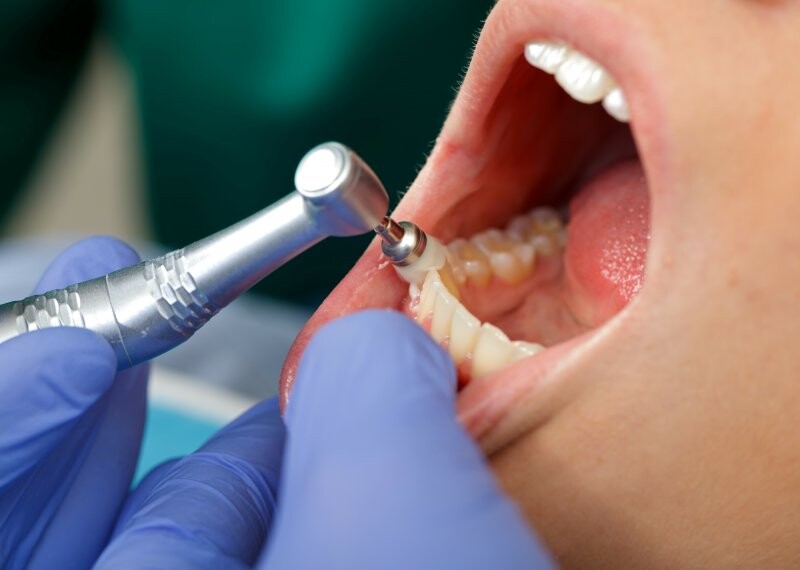

What defines a professional teeth cleaning?

Much more thorough than the brushing and flossing you do at home, a dental teeth cleaning – or dental prophylaxis – is a professional dental procedure that removes plaque, stains, and calculus (also known as tartar) that have built up above your gum line. Your hygienist uses specific tools to scrape away these deposits, either hand tools – the scrapers and picks you’re likely familiar with – or, if needed, an electronic device called an ultrasonic scaler for deeper stains or discolorations. Once your teeth are clean, they’re polished with a prophylaxis paste specifically formulated for this use.